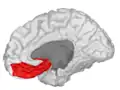

Basal surface of cerebrum. Orbital gyrus shown in red.

Medial orbitofrontal cortex, inner slice view.